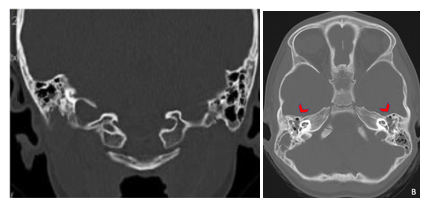

A subsequent CT scan of the brain, complete abdomen, and thorax showed soft tissue lesions that were homogeneous, well defined, and exhibited mild enhancement with contrast, eroding and altering the morphology of the skull cortex without infiltrating the brain parenchyma (Figure 2A & 2B). Additionally, multiple lytic lesions were identified in the sphenoid bone and vertebral bodies of C2, C3, and C5 vertebrae. Thoracic CT revealed lytic lesions in the vertebral bodies of T1, T3, T4, T6, and T7, along with pathological fractures of T5 and T9 (Figure 3A & 3B). Given the extensive bone involvement, the possibility of aggressive systemic disease was considered, including LCH, neuroblastoma, and metastatic rhabdoid tumors. Definitive histopathological examination of the previously biopsied tissue, complemented by immunohistochemistry, confirmed the diagnosis of Langerhans cell histiocytosis (LCH). Immunohistochemical staining was positive for S-100, CD68, PD-L1, and CD1a, which further confirmed the diagnosis. Due to the patient developing bilateral ear discharge, a mastoid CT scan was performed. The scan showed a loss of normal mastoid morphology with bony erosion caused by homogeneous soft tissue lesions bilaterally (right mastoid: 2.9 x 1.8 cm, left mastoid: 3.4 x 2.3 cm) (Figure 4A & 4B). These findings are consistent with the systemic spread of LCH, which affects the temporal bones.

Figure 4A&4B Mastoid CT of the patient revealed total opacification of the remaining mastoid air cells and loss of morphology of both mastoid portions of the temporal bone.